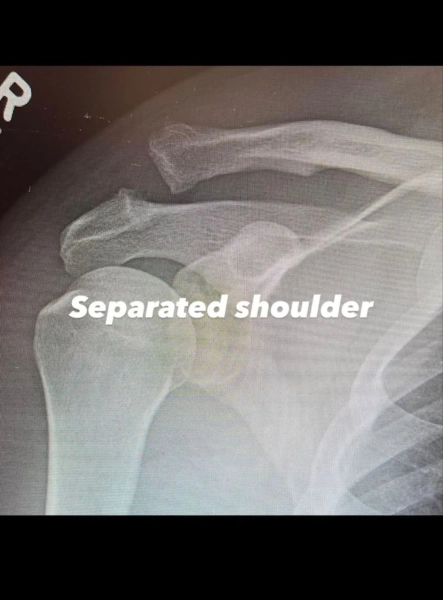

Як стало відомо, операція була необхідною внаслідок вивиху акроміально-ключичного суглоба. Щоб повернути плече у правильне положення, лікарям знадобилося здійснити хірургічну процедуру.

Додатково, актор розмістив рентгенівські знімки плеча до та після операції. Ченнінг Татум не розкрив деталі отримання травми, але запевнив, що має намір перебороти труднощі та повністю оздоровитися.